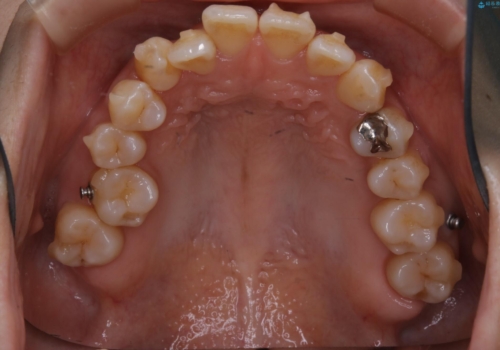

- 上の前歯は内側に入っていることが気になりご相談にいらした方です。インビザラインにて治療を行いました。

1週間でのマウスピース交換を指示していましたが、20時間以上使えない時があると不安との事で、2週間ごとの交換にしていました(実際はほとんど20時間以上使用できていたようです)。治療終了まで時間はかかりましたが、最終的に綺麗に並べることができ、大変喜んでいただけました。